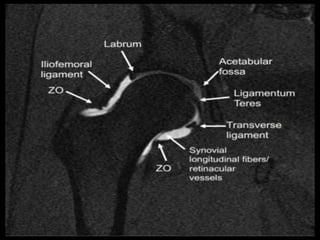

Hip Joint.